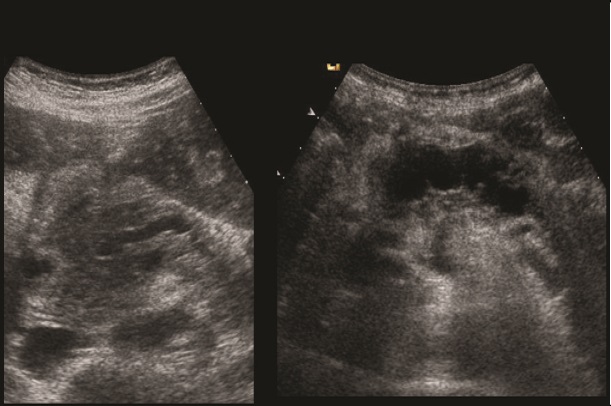

. Echographie :

Image echographique

percutanee direct de

pancreatite chronique est image de hyperechogene

heterogeneite de la

parenchyme pancreatique , sa taile peut augemente ,

normalement ou diminue sa bord est irregulier ,parfois

en presente des nodules calcification parenchymeteuse ou bien

image calcaire des calculs du canal pancreatique ce qui donne

de aspect de cone de l.ombre posterierure, en ce cas les

canal intra pancreatique sont dilates .

Les faux kyste associe peut en presente et se donne des images aechogene ou

hypoechogene intrapancreatique . Imge de ascite parfois se

en voyait